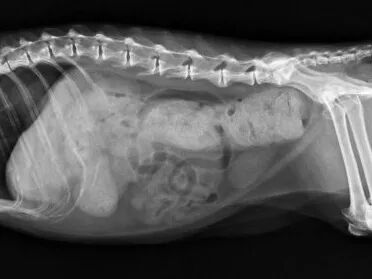

患有巨结肠猫咪的肚子